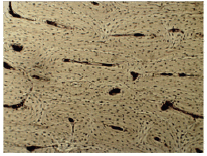

A imagem abaixo representa o tecido ósseo visto em um microscópio óptico com um aumento de 400 x.

Sobre o tecido apresentado na imagem, analise as seguintes afirmativas:

I- É um tecido avascular.

II- Contém células vivas denominadas osteócitos, osteoblastos e osteoclastos.

III- A matriz extracelular contém fosfato de cálcio responsável pela rigidez do osso.

Assinale a afirmativa correta: